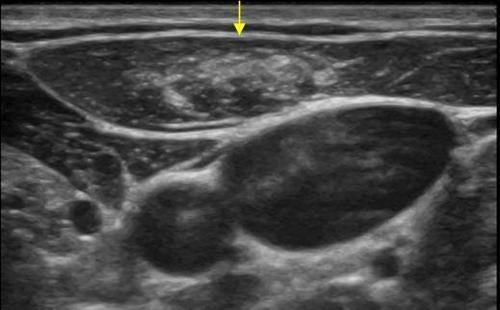

Lenf bezleri doğuştan vücudumuzda bulunan ve vücudumuzun mikroplara karşı ilk koruyucu tabakalarıdır. Enfeksiyon ajanları ile karşılaşınca büyürler, enfeksiyon tedavi edilince ya da vücut tarafından etkisiz hale getirilince küçülürler. Ayrıca lenf bezleri bir takım hematolojik kan hastalıkları (lenfoma, lösemi vb.) ve bazı kanserlerde de etkilenirler ve büyürler. Büyümüş bir lenf bezinin enfeksiyona mı yoksa kansere mi bağlı olduğunu anlamakta ultrasonu çok önemli bilgiler vermektedir. Buna göre de hastanın takip, medikal tedavi ve biyopsi kararı verilmektedir.